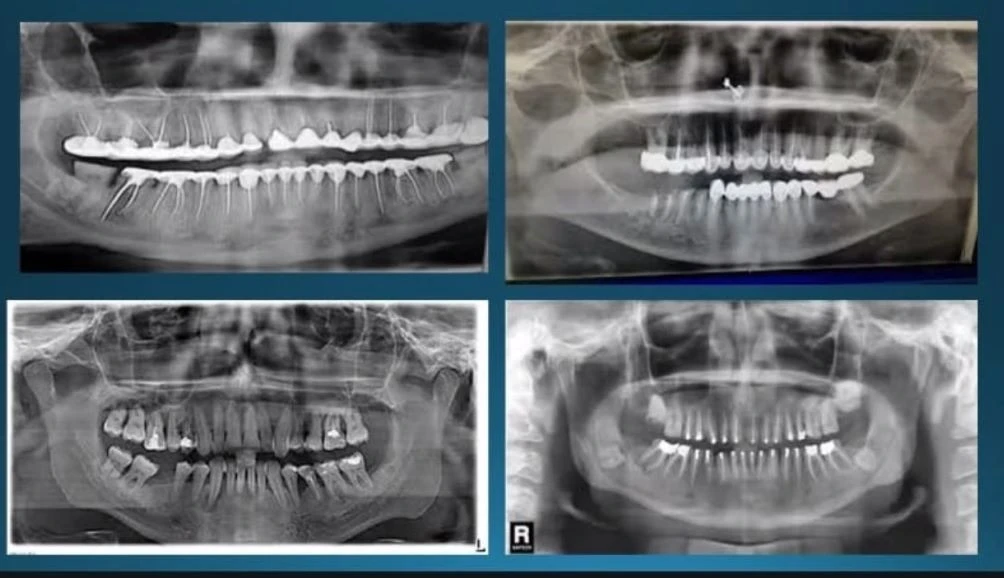

Diagnosis ini melibatkan evaluasi gejala klinis, riwayat pasien, pemeriksaan radiografis, hingga uji vitalitas pulpa. Tujuannya adalah membedakan apakah pulpa masih dalam kondisi sehat, mengalami inflamasi reversibel, atau sudah irreversibel yang memerlukan perawatan lebih lanjut.

"Pemeriksaan juga menilai adanya infeksi maupun kelainan pada jaringan periapikal, seperti abses atau granuloma," lanjut Dr Epita.